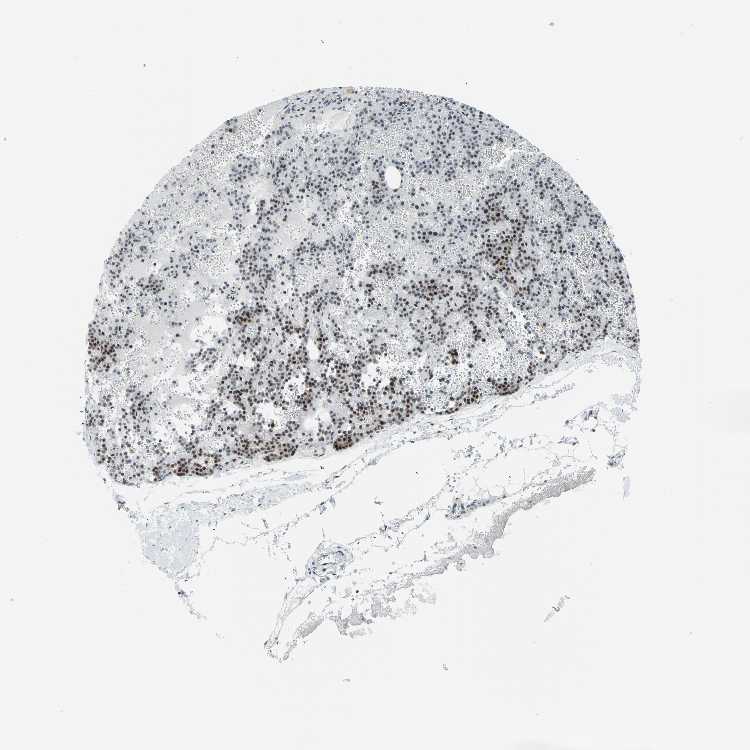

PARATHYROID GLAND - Antibody stainingi

Antibody staining in the annotated cell types in the current human tissue is reported as not detected, low, medium, or high, based on conventional immunohistochemistry profiling in selected tissues. This score is based on the combination of the staining intensity and fraction of stained cells.

Each image is clickable and will lead to virtual microscopy that enables deeper exploration of all samples and also displays staining intensity scores, fraction scores and subcellular localization as well as patient and tissue information for each sample.

Antibody CAB008087

Glandular cells Medium